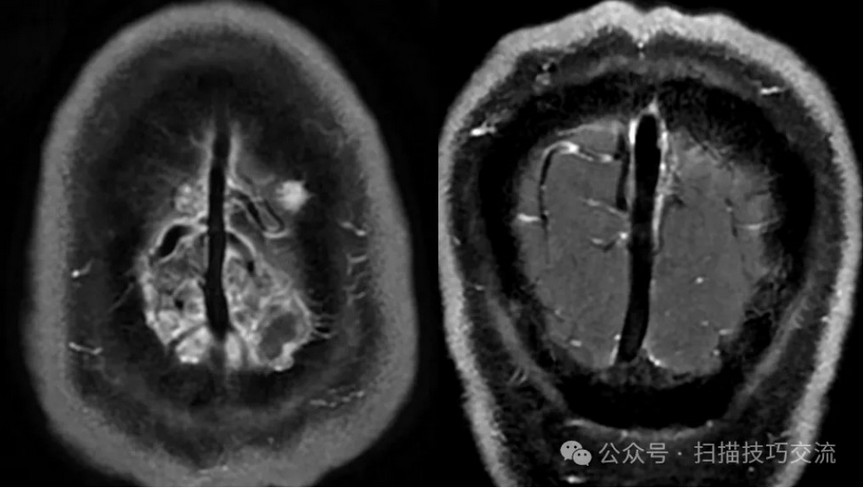

临床申请:颅脑平扫,静脉成像,磁敏感成像,颅内静脉血管黑血成像。

颅内静脉黑血成像,CUBE T1fs w/o +c,静脉窦未见异常。